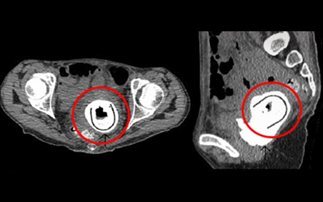

Οι γιατροί έβαλαν τη γυναίκα στο χειρουργείο και τότε ήταν που έπαθαν σοκ! Δεν μπορούσαν να πιστέψουν ότι αυτό που έβλεπαν στους υπερήχους -και εκείνη τη στιγμή ζωντανά- ήταν ένα ερωτικό παιχνίδι μήκους 11 εκατοστών. Τελικά, η γυναίκα παραδέχτηκε ότι το είχε χρησιμοποιήσει με τον σύντροφο της πριν 10 χρόνια και εξήγησε ότι επειδή ήταν μεθυσμένη δε μπορούσε μετά να θυμηθεί αν το είχε αφαιρέσει ή όχι από το σώμα της!

Μετά από ένα μεθύσι ξέχασε να αφαιρέσει το ερωτικό παιχνίδι, που φαίνεται εδώ κυκλωμένο.